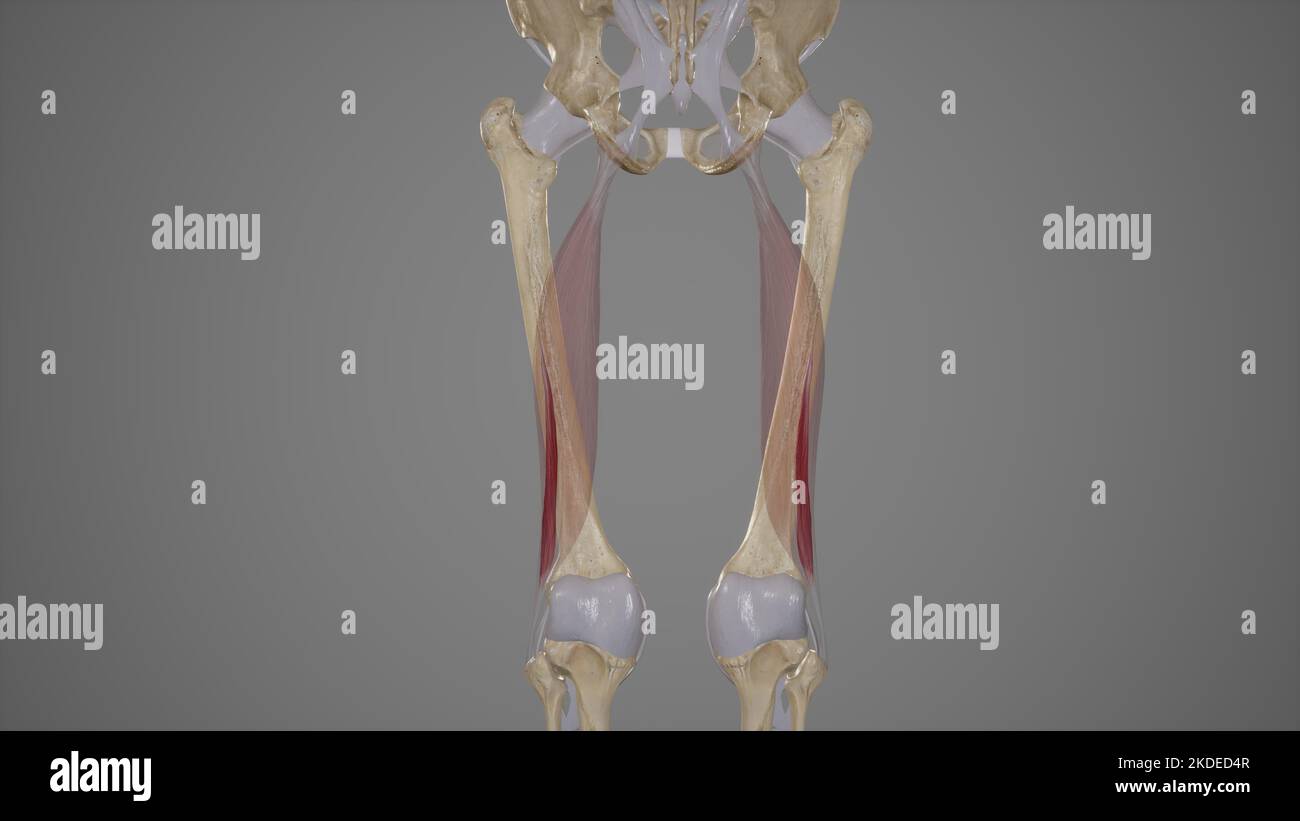

Illustration médicale précise de la tête courte du biceps Femoris Banque D'Imageshttps://www.alamyimages.fr/image-license-details/?v=1https://www.alamyimages.fr/illustration-medicale-precise-de-la-tete-courte-du-biceps-femoris-image490198487.html

Illustration médicale précise de la tête courte du biceps Femoris Banque D'Imageshttps://www.alamyimages.fr/image-license-details/?v=1https://www.alamyimages.fr/illustration-medicale-precise-de-la-tete-courte-du-biceps-femoris-image490198487.htmlRF2KDED4R–Illustration médicale précise de la tête courte du biceps Femoris